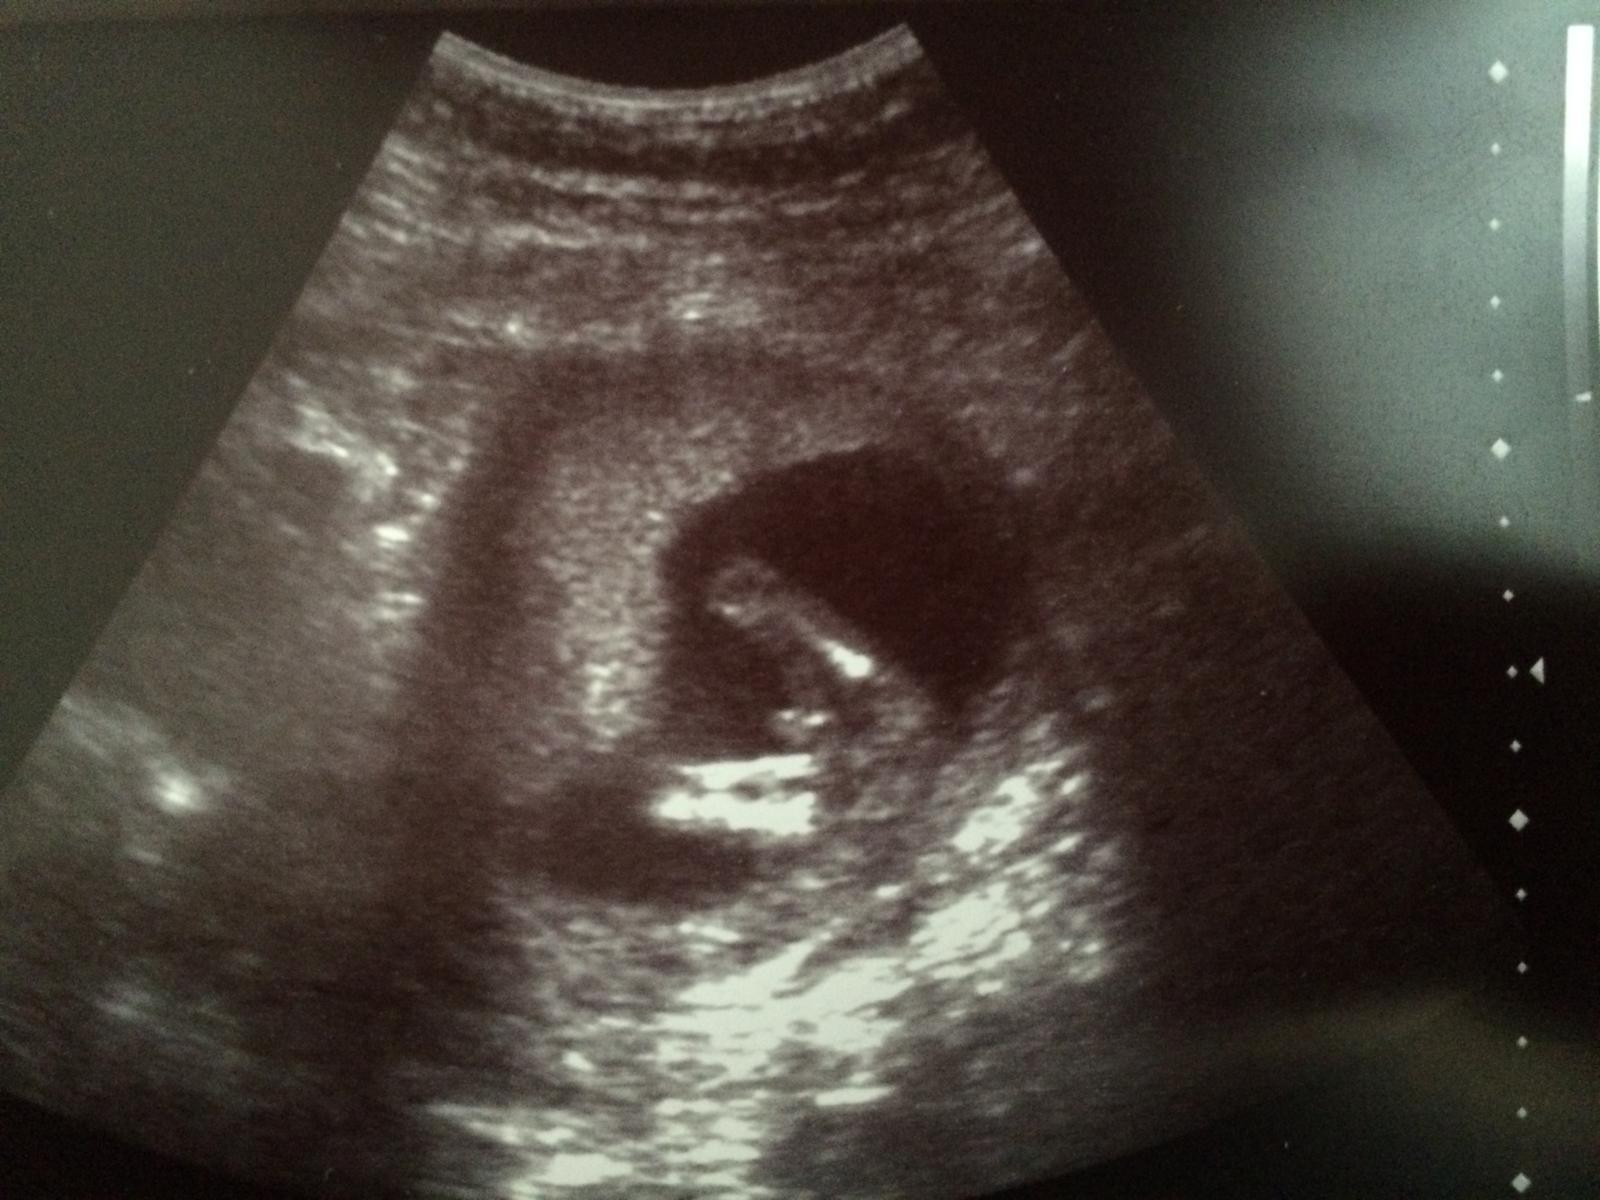

@nicolettka2126 vobec netusime ako sa bude volat 🙂, no lekar zapol sono, pomeral a hovori, kuknem este pohlavie a maly sups a nohy odseba 🙂 baby ja som spokojna, Viktorkovi hovori lekar budes mat braceka a Viktorko zacal ze Hura hura bracek. podla mna bol mimo z toho co videl 🙂 ale ja som stastna, chalana som chcela 😉

@nicolettka2126 mojko no to roztiahnutie noh, to som sa pobavila a aj ja som hned videla ze aha pipik 🙂, nakoniec nam vyslo to co sme si aj mysleli 🙂, aspon ked budeme s nimi chodit von, nebudu sa nam bit o hracky 🙂 moj sa bude hrat s autickami a tvoja s babikami 🙂

My ked sme boli na 3D tak nam dr povedala ze od hlavicky po zadocek ma mala 10,4cm a plus este nozky k tomu cize dokopy okolo 16cm 🙂